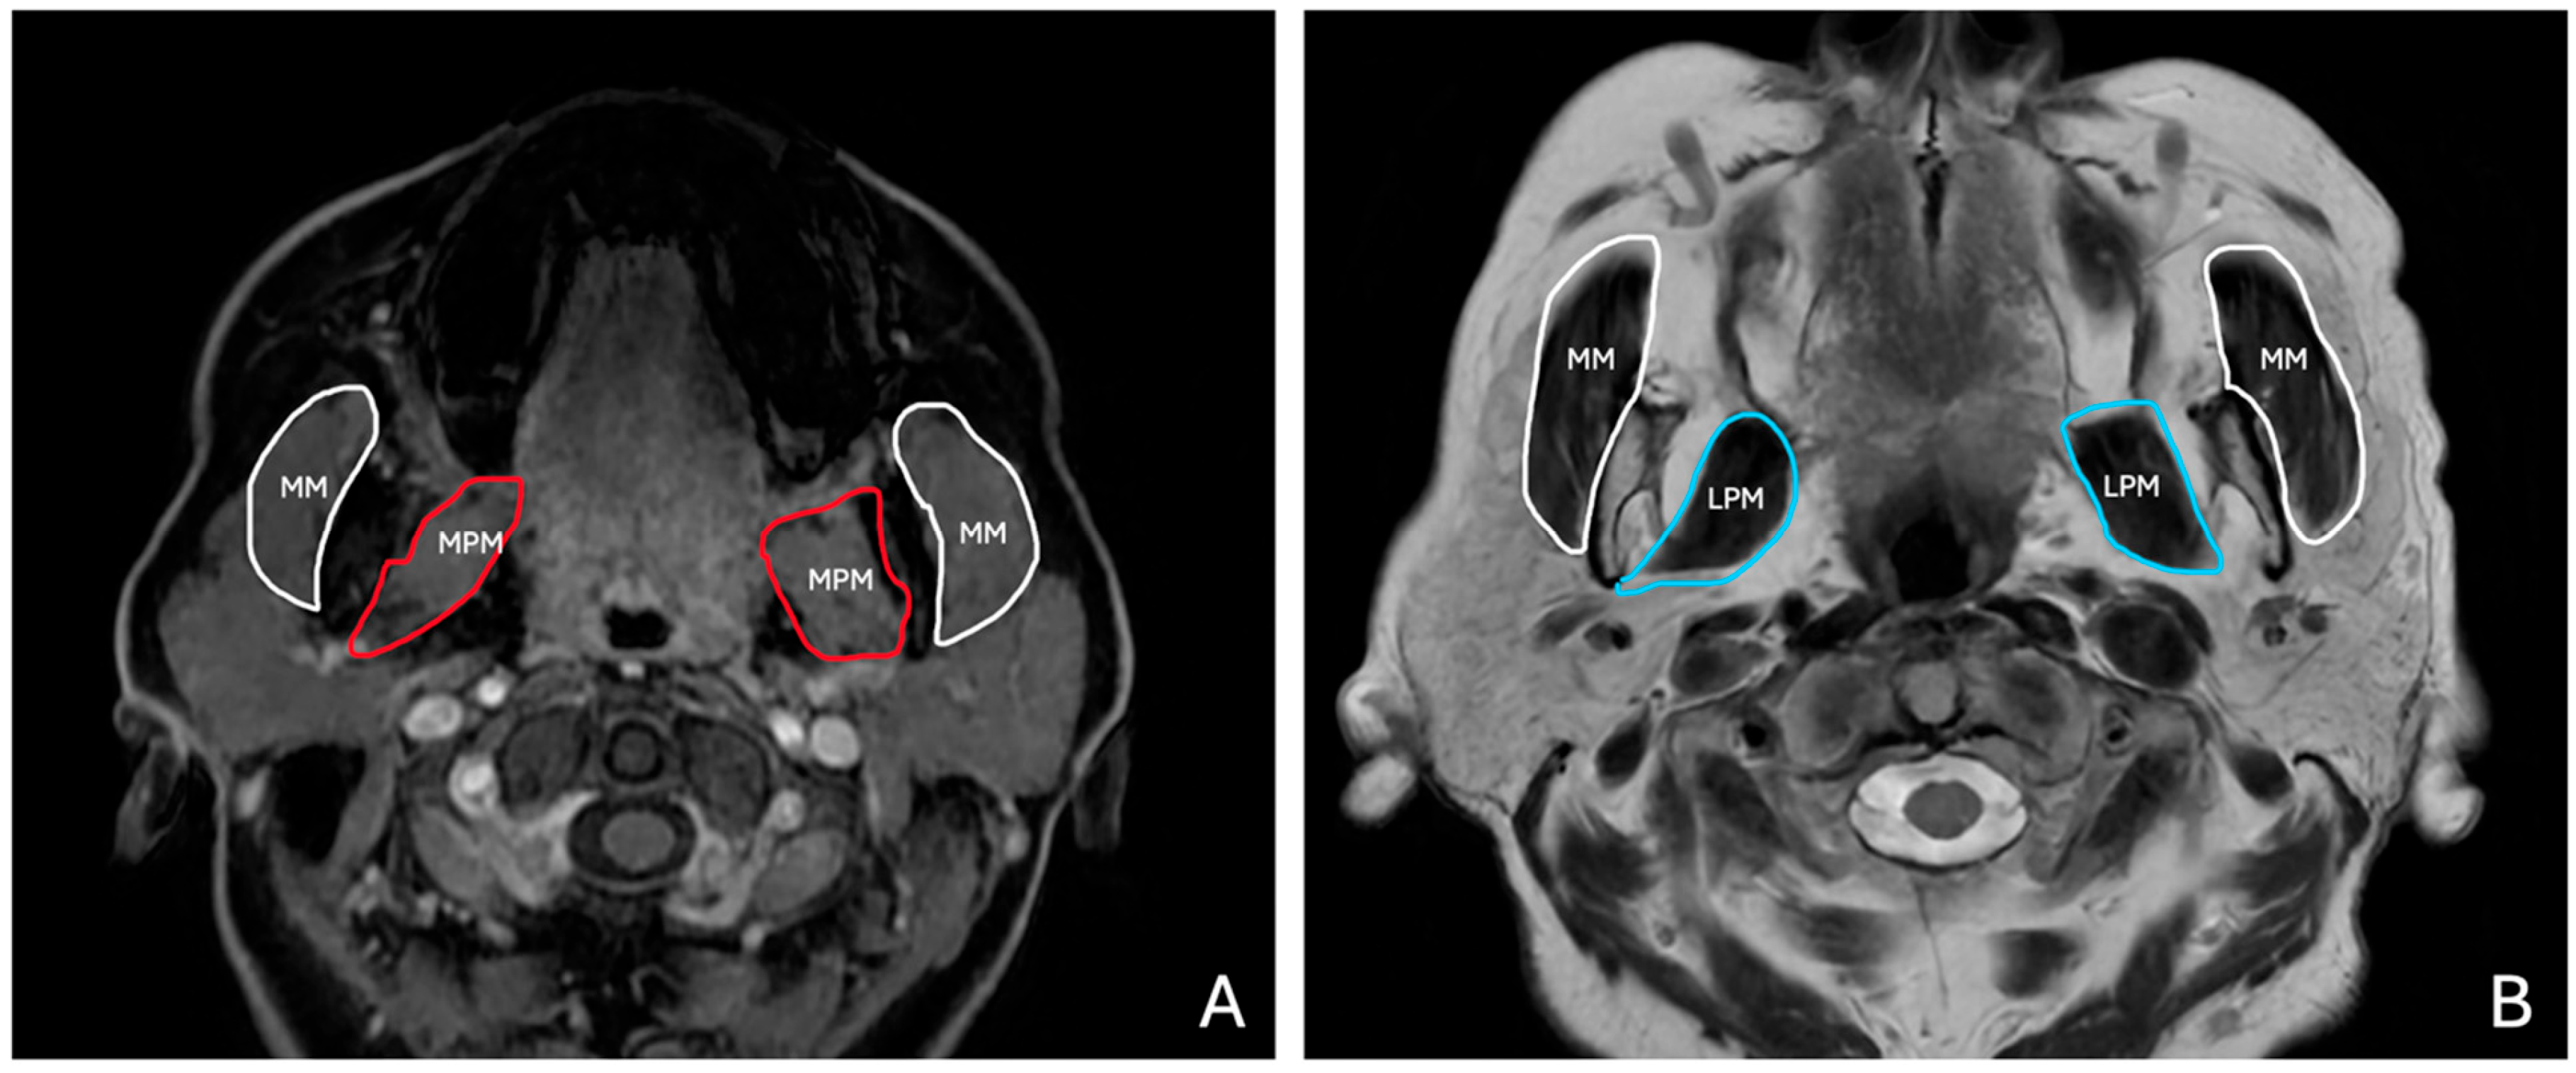

T1W and T2W axial images were used to evaluate the masticatory muscles bilaterally (Figure 2). Measurements were taken at predefined anatomical landmarks to ensure reproducibility, as follows:

Figure 2. (A) Axial LAVA T1-weighted MR image shows masseter (MM, white) and medial pterygoid muscles (MPM, red). (B) T2-weighted FSE MR image shows masseter (MM, white) and lateral pterygoid muscles (LPM, blue).